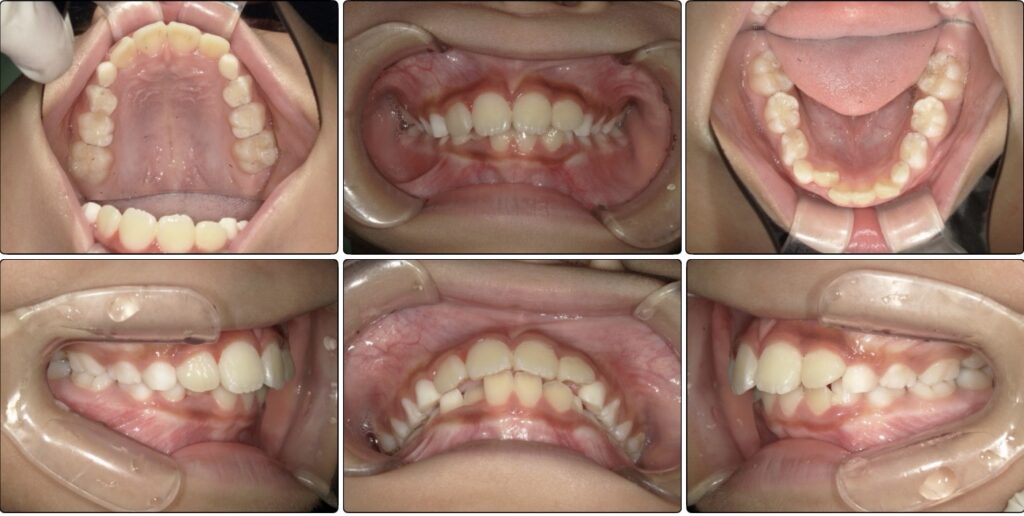

最初の検査時に撮影した写真です。

お母さんが気にされていた前歯が大きいという点ですが、歯が大きく見えるのは噛み合わせの状態や、顎の骨の成長が足りていないケースも考えられます。

下の歯が隠れており、前歯の存在が大きく感じます。

下の歯並びは2番目の歯が後ろから生えてきており、スペースが足りないようでした。